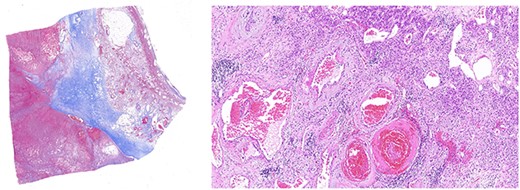

Left panel: low magnification (20×) of Masson’s trichrome stain highlighting fibrosis, fibrin and haemangioma in the adrenal cortex. Right panel: medium magnification (200×) of haematoxin- and eosin-stained section demonstrating variably dilated vascular changes filled with blood with variable hyalinization and fibrin in the wall.